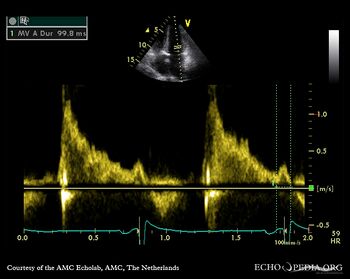

A3CH Pulsed-wave Doppler signal of mitral inflow: E>A

Pulsed-wave Doppler signal of mitral inflow Pulsed-wave Doppler signal of pulmonary venous flow: A